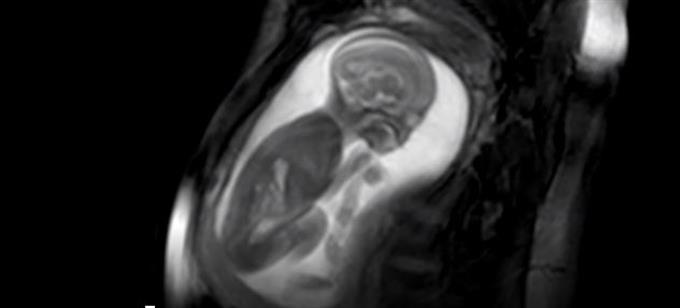

Επίθεση κατά της Νέας Δημοκρατίας εξαπολύει ο ΣΥΡΙΖΑ για την υφυπουργοποίηση της Χριστίνας Αλεξοπούλου, η οποία σε τοποθετήσεις της παρελθόν είχε υιοθετήσει τη θεωρία του «αγέννητου παιδιού»